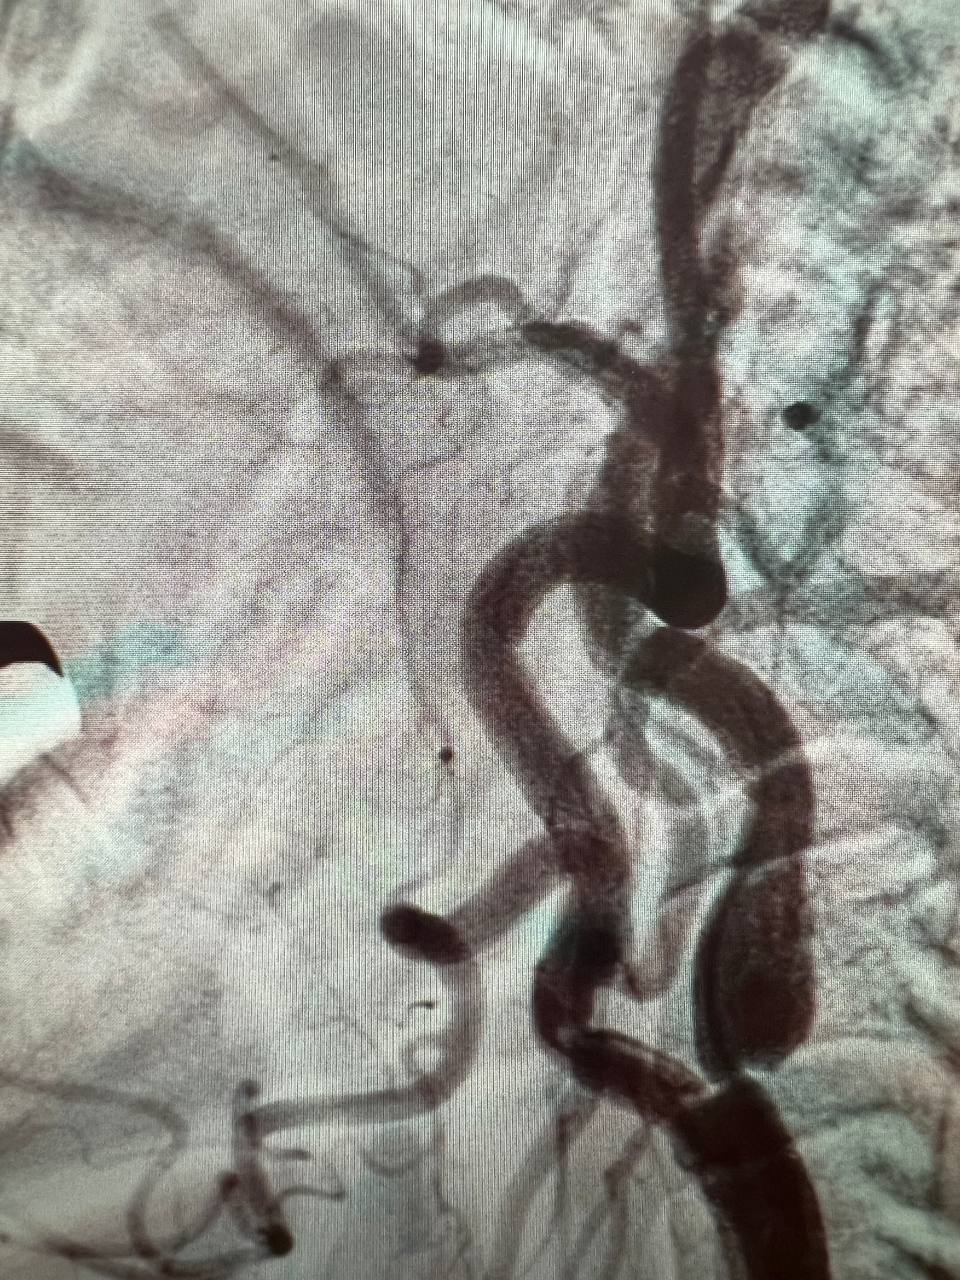

На ангіографічній системі Infinix 2011 року випуску вперше в історії госпіталя провели ургентне стентування та балонну ангіопластику лівої внутрішньої сонної артерії.

У відділення неврології поступив пацієнт з повторним ішемічним атеротромботичним інсультом в басейні лівої СМА  з елементами моторної афазії. Атеросклеротична субоклюзія (85%) С1 сегменту лівої внутрішньої сонної артерії. Дисліпідемія. Гіпертонічна хвороба ІІІ ст., 3 ст., ризик 4.

Терміново проведено ургентне оперативне втручання: ендоваскулярне стентування стенотичного ураження гирла С1 сегменту лівої внутрішньої сонної артерії. Селективна церебральна ангіографія. Це була дуже складна операція, але пройшла успішно. Відкрили ЛВСА на 90%.

Результати дослідження до та після ургентного оперативного втручання: